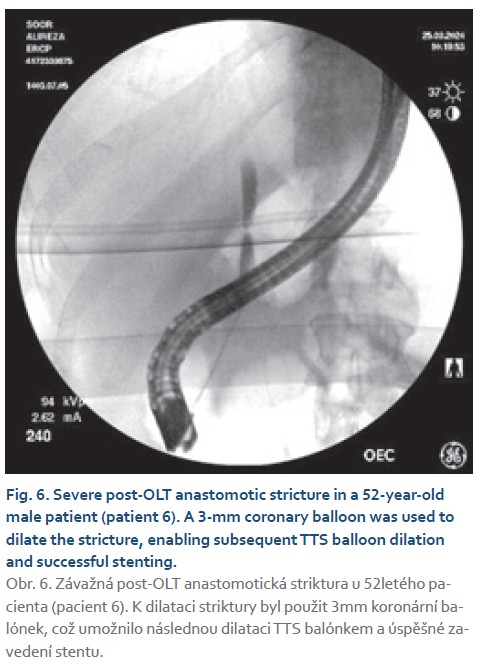

- patient 6: 52-year-old male with post- -OLT anastomotic stricture.

- patient 6: an anastomotic stricture post-OLT was effectively dilated using a coronary balloon, facilitating subsequent TTS balloon use and stenting.